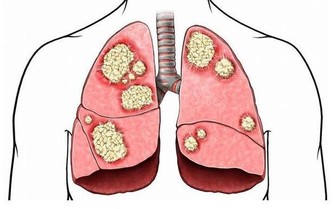

11、痛風、高尿酸血症

都是血液中尿酸過多造成的

血液尿酸高的人,

尿酸會沈積在腎臟裡,使腎功能受損傷。